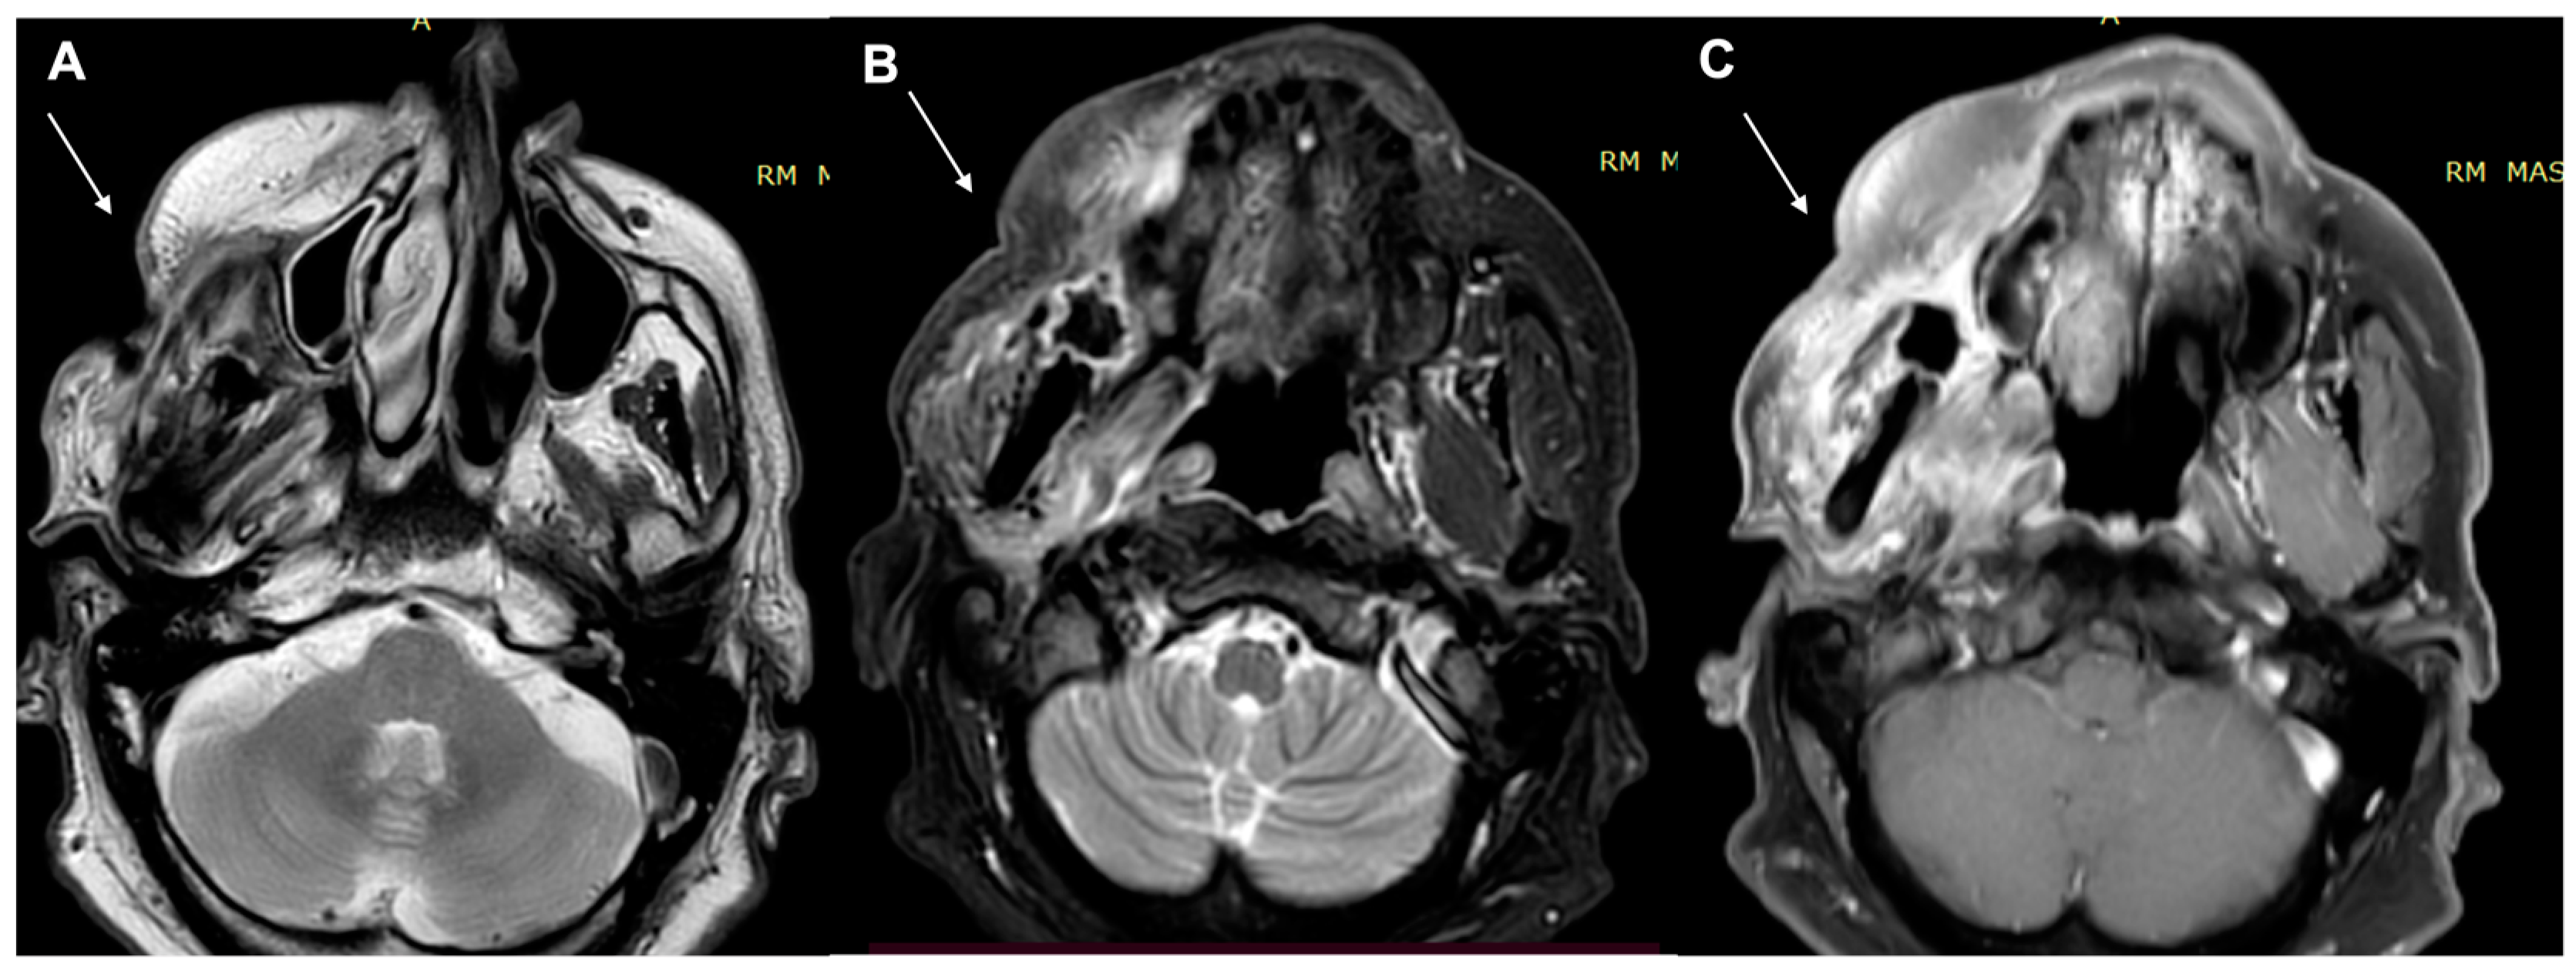

2. Diagnostic Imaging and Non-Melanoma Skin Cancer

3. Diagnostic Tools and Non-Melanoma: Staging and Surveillance